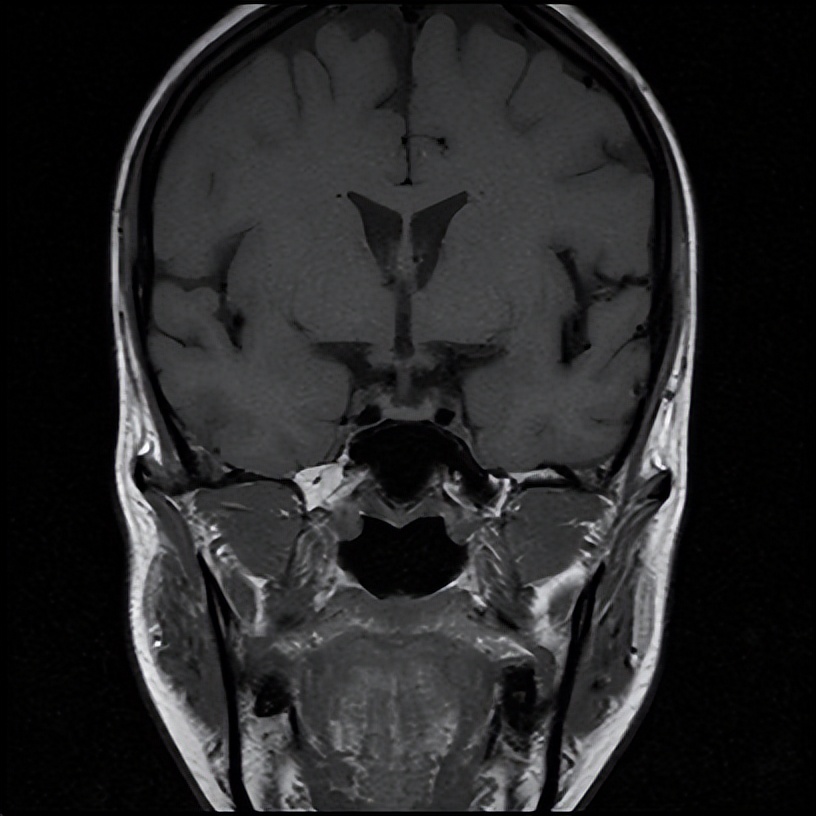

住院期间,银主任经过详细的询问病史和查体,为王女士有针对性地完善了相关检验、检查,入院急查血钠107.0mmol/L,血氯76.0mmol/L(参考范围96-108mmol/L),经积极补钠、护胃及对症支持治疗后王女士的血钠稳步上升,症状逐渐减轻,相关结果回报上午皮质醇、促肾上腺皮质激素(ACTH)水平降低,垂体磁共振未见明显异常。会不会是内分泌方面的因素导致低钠血症呢?深圳大学总医院内分泌代谢病科派驻罗城县人民医院内四科的丘雅维主治医师应邀会诊。丘医生分析患者体型消瘦,皮肤黏膜无明显色素沉着,低血压,轻度贫血,白细胞及中性粒细胞、血糖和糖化血红蛋白均偏低、低钠低氯、上午皮质醇和ACTH水平降低,初步考虑继发性肾上腺皮质功能减退可能性大,并对患者垂体磁共振再次阅片,发现垂体组织受压变扁,表现为部分性空泡蝶鞍。请深圳大学总医院影像科派驻罗城县人民医院影像科的杨智钧主治医师阅片后也支持部分性空泡蝶鞍的影像学诊断。

注:箭头所指为受压变扁的垂体。

那么什么叫空泡蝶鞍呢?所谓空泡蝶鞍综合征,是因鞍膈缺损或垂体萎缩,蛛网膜下腔在脑脊液压力下疝入鞍内,其中脑脊液填充,致蝶鞍扩大变形,垂体受压变平而产生的一系列临床变现,患者可出现头痛、视野缺损、垂体功能异常等表现。而垂体功能异常可显现为一种或多种垂体相关激素水平异常,如影响到肾上腺皮质轴导致肾上腺皮质功能减退,患者可出现头晕、血压降低、食欲减退、恶心呕吐、疲乏无力、消瘦、低血糖、低血钠等表现。